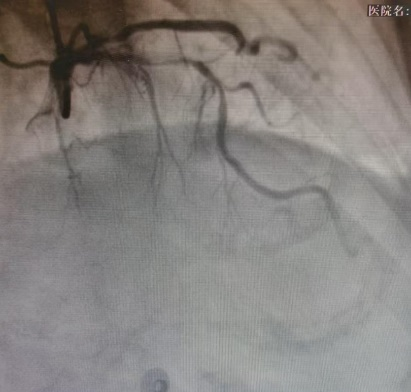

患者吕奶奶今年71岁,因反复严重胸痛入院。冠状动脉造影结果令医生们深吸一口气:心脏最重要的“生命主干道”——左前降支近段,被严重钙化斑块紧紧堵塞,狭窄程度超过95%,血管壁坚硬如石,在X光下呈现出典型的“脊背样”钙化影,IVUS显示360度环形钙化。

冠脉造影显示前降支严重狭窄伴钙化

IVUS显示前降支环形钙化